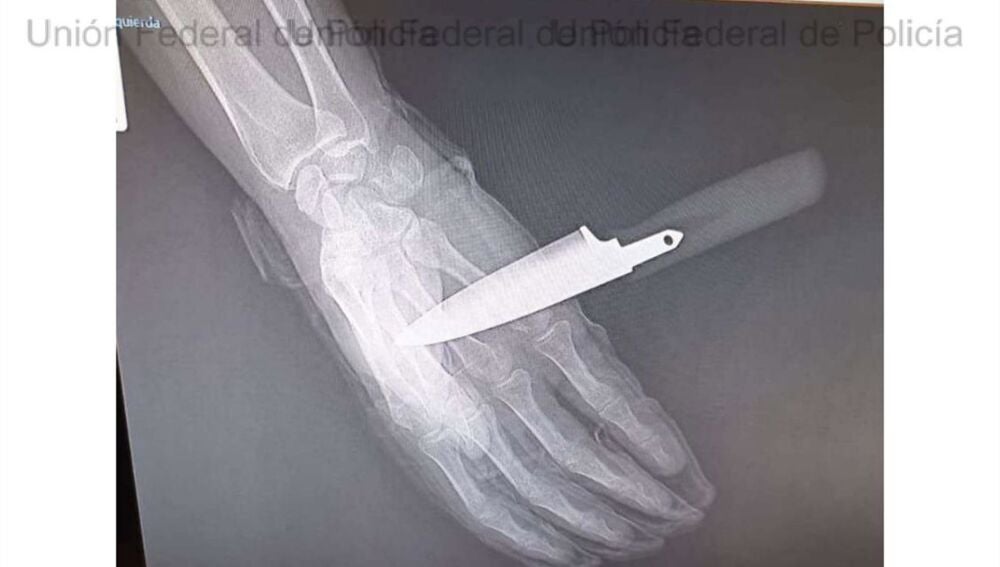

Radiografía de la mano del agente de la Policía Nacional apuñalado en Baza | UNIÓN FEDERAL DE POLICÍA (UFP)

Tras el primer ataque, el agresor intentó asestar una segunda puñalada, que el agente logró repeler parcialmente. No obstante, el arma blanca llegó a atravesarle la mano, provocándole heridas de consideración.

A pesar de las heridas, el policía consiguió reaccionar haciendo uso de su defensa extensible reglamentaria. Con la colaboración de su compañera, logró reducir y detener al atacante, que fue trasladado a dependencias policiales e ingresado en calabozos. Por su parte, el agente herido tuvo que ser evacuado a un centro hospitalario, con el cuchillo aún clavado en la mano, donde recibió atención médica.